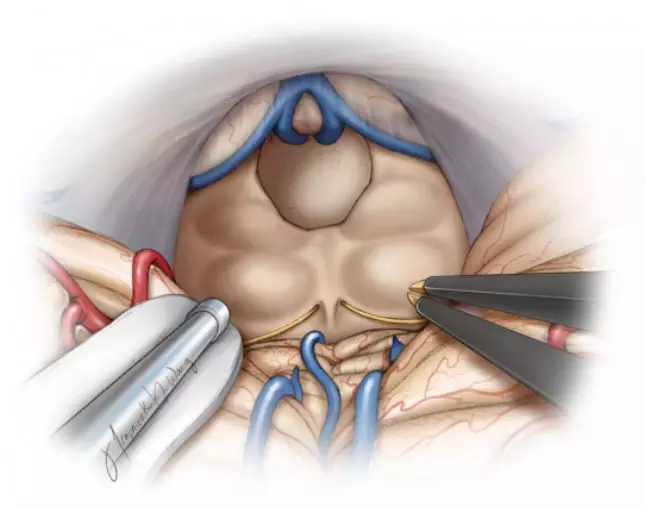

图5. 后正中小脑上入路常被用于暴露顶盖区。三脑室后部肿瘤经常影响顶盖上方并使丘脑枕后部移位。笔者首先要确定间脑静脉的位置(包括Galen静脉),若其向后移位(使静脉处在术者和肿瘤之间)则不利于建立手术通道。肿瘤也可能包绕这些静脉,在手术早期阶段可能会不小心损伤。

图6. 经顶盖区暴露范围有限。在这些病例中,可用环形刮匙从脑室内刮除肿瘤。